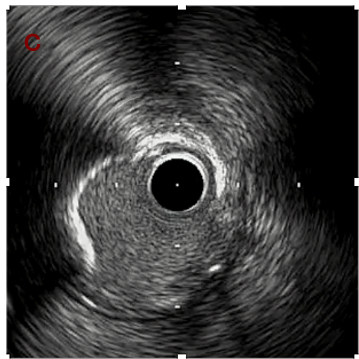

IVUS after OAS high speed 3回

IVUS imaging after high speed 3回

a,b,cはさらに石灰化に食い込み、石灰化量は減少。

それに伴いdではbiasがさらにtentingのIVUS所見にへんかしhigh injury riskと思われた。

引き続き造影で確認してpinpointで引きのOAS high speedを3回さらに追加のためcでIVUSマーキングを行い、その点より引きで赤線のpinpoint OAS high speedを行い、dに関してはinjury回避のためにOASを当てない方針とした。